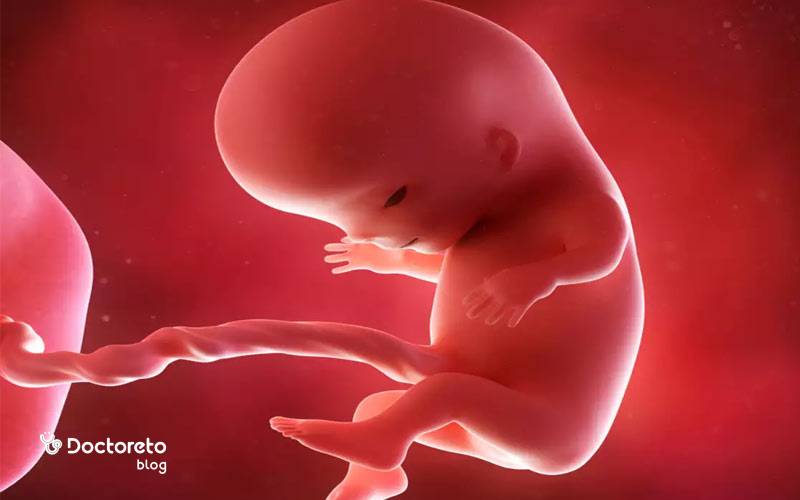

در جنین ۱۱ هفتهای، نسبت سر به بدن هنوز بزرگتر است اما گردن مشخصتر شده و بدن از حالت خمیده ابتدایی خارج میشود. انگشتها و انگشتان پا از هم جدا شدهاند، مفاصل زانو و آرنج فعالترند و جوانههای دندانی اولیه شکل گرفتهاند. کبد هنوز نقش پررنگی در خونسازی دارد و رودهها که تا همین حوالی در بند ناف بودند، بهتدریج به داخل شکم برمیگردند. شکل جنین در هفته یازدهم بارداری در سونوگرافی با ستون فقرات روشن و حرکات جهشی کوتاه قابلمشاهده است.

از نظر عملکرد، مسیرهای عصبی و مخچه رشد میکنند و همین باعث افزایش حرکات بازتابی میشود. بااینحال شما هنوز این حرکات را حس نمیکنید. پوست جنین نازک و نیمهشفاف است و عروق زیر آن دیده میشوند. استخوانسازی جنین 11 هفته آغاز شده و استخوانهای بلند پا و ساعد در تصاویر سونو نمایانترند. همه این تغییرات جنین ۱۱ هفته ای زمینه جهش رشدی سهماهه دوم را فراهم میکند. مهمترین تغییرات جنین در هفته یازدهم حاملگی عبارتند از:

شکل جنین در هفته یازدهم بارداری متقارنتر میشود؛ صورت با نزدیکی تدریجی چشمها به خط میانی، تشکیل پلکهای بسته و مشخصتر شدن بینی و لب بالا دیده میشود. انگشتان دست و پا شکل میگیرند و ناخنها تشکیل میشوند. دست و پای قورباغهای در این هفته بهطور کامل از بین میروند و جنین شبیه به نوزاد میشود. دستها در مچ خم میشوند، پاها کشیدهتر شدهاند و حرکات لگد مانند کوتاه در سونوگرافی مشاهده میشود. طنابنخاعی و مهرهها بهصورت خطوط روشن موازی مشخصاند. جنین تقریبا اندازه یک انجیر است.